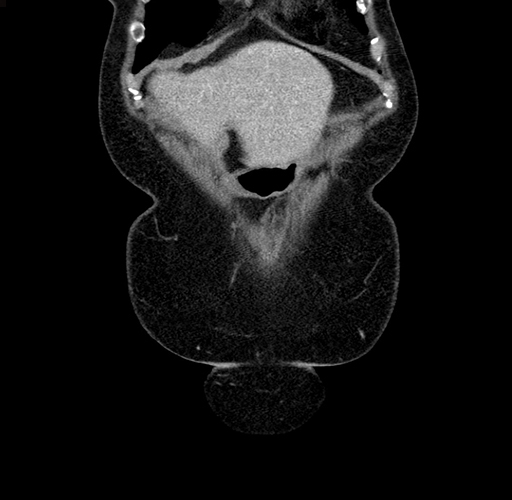

Pre-Chemo: Coronal Venous

Coronal Venous